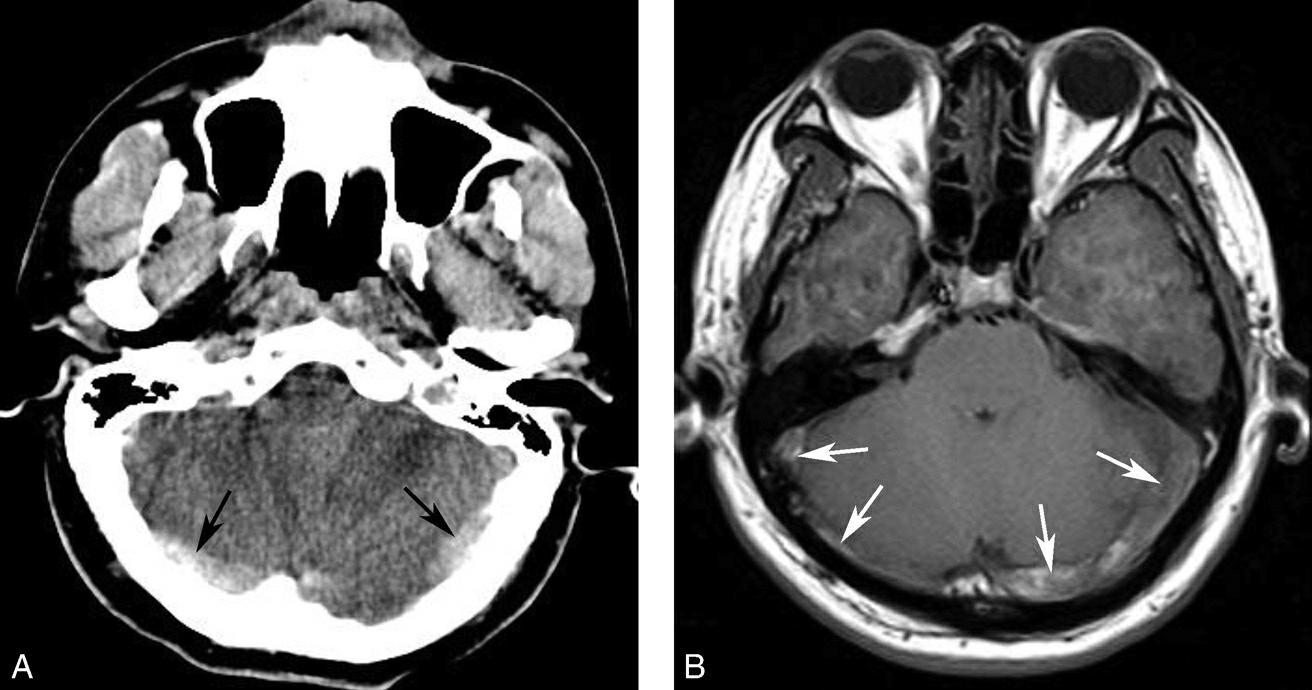

蝶鞍两侧为海绵窦,其内包含颈内动脉及第Ⅲ~Ⅵ对脑神经。海绵窦的密度升高或体积增大常提示病变存在。海绵窦外侧为颞叶,两者之间隔以海绵窦外侧壁。鞍背后方为桥前池及其后方的脑桥,桥前池内可见基底动脉断面,呈圆形稍高密度影。层面中部两侧为颞骨乳突部,其内气化的骨性腔隙为乳突气房。脑桥后方为第四脑室,呈半圆形或新月形,小脑半球的病变(如肿瘤、炎症、出血等)常压迫第四脑室,导致其变形甚至闭塞(图1-2-13)。两侧小脑半球间为小脑蚓部。小脑半球与颞骨乳突部间可见乙状窦。小脑蚓部后方为直窦与上矢状窦汇入窦汇处,窦汇两侧为横窦。静脉窦血栓时可见上述静脉窦增宽、密度明显升高(图1-2-14)。

图1-2-14 静脉窦增宽、密度升高(静脉窦血栓)

男,47岁,头痛2周,意识模糊2天,无头颅外伤史。A.CT平扫示双侧横窦增宽、密度增高(黑箭),提示静脉窦血栓;B.MRI T 1 WI提示双侧乙状窦、横窦血栓形成(白箭)